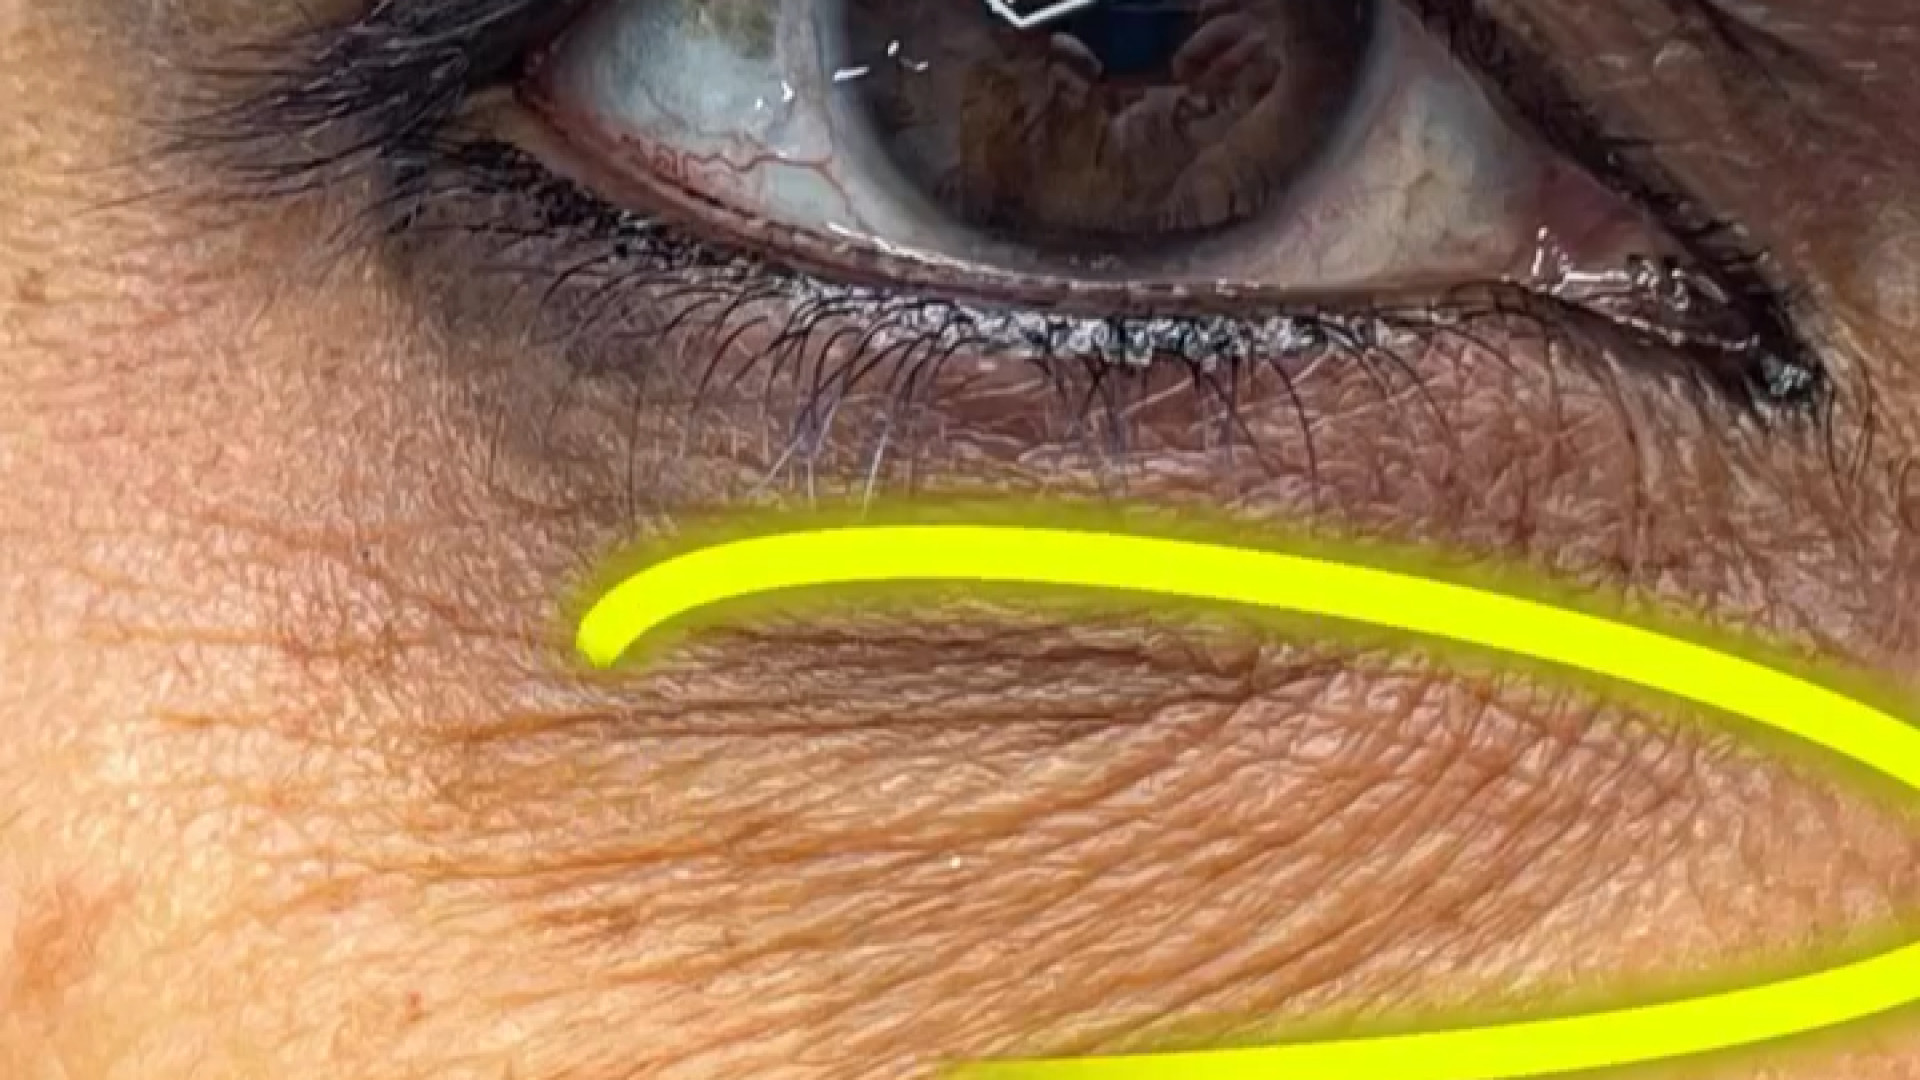

سیاهی و گودی زیر چشم عارضهای شایع است که به دلایل مختلفی از جمله ژنتیک، خستگی، کمآبی بدن، آلرژی و افزایش سن ایجاد میشود. این مشکل میتواند باعث شود افراد پیرتر و خستهتر به نظر برسند. خوشبختانه، روشهای مختلفی برای درمان سیاهی و گودی زیر چشم وجود دارد، از جمله استفاده از کرمهای مراقبتی، تغییر سبک زندگی و انجام روشهای درمانی پزشکی.

تزریق زیر چشم یک روش غیرجراحی است که در آن از مواد پرکننده (فیلر) برای پر کردن گودی و رفع سیاهی زیر چشم استفاده میشود. این روش میتواند به بهبود ظاهر چشمها، کاهش خستگی چهره و افزایش اعتماد به نفس کمک کند. تزریق زیر چشم باید توسط پزشک متخصص و با تجربه انجام شود تا از بروز عوارض احتمالی جلوگیری شود.

این روش با تزریق دقیق فیلرهای هیالورونیک اسید به ناحیه زیر چشم، حجم از دست رفته را جبران کرده و باعث میشود پوست این ناحیه صافتر و روشنتر به نظر برسد. این فرآیند، با تحریک تولید کلاژن، به مرور زمان به بهبود کیفیت و استحکام پوست نیز کمک میکند.

علاوه بر این، تزریق زیر چشم میتواند به بهبود کیفیت پوست در این ناحیه نیز کمک کند. فیلرهای هیالورونیک اسید با جذب آب، باعث آبرسانی و جوانسازی پوست میشوند.